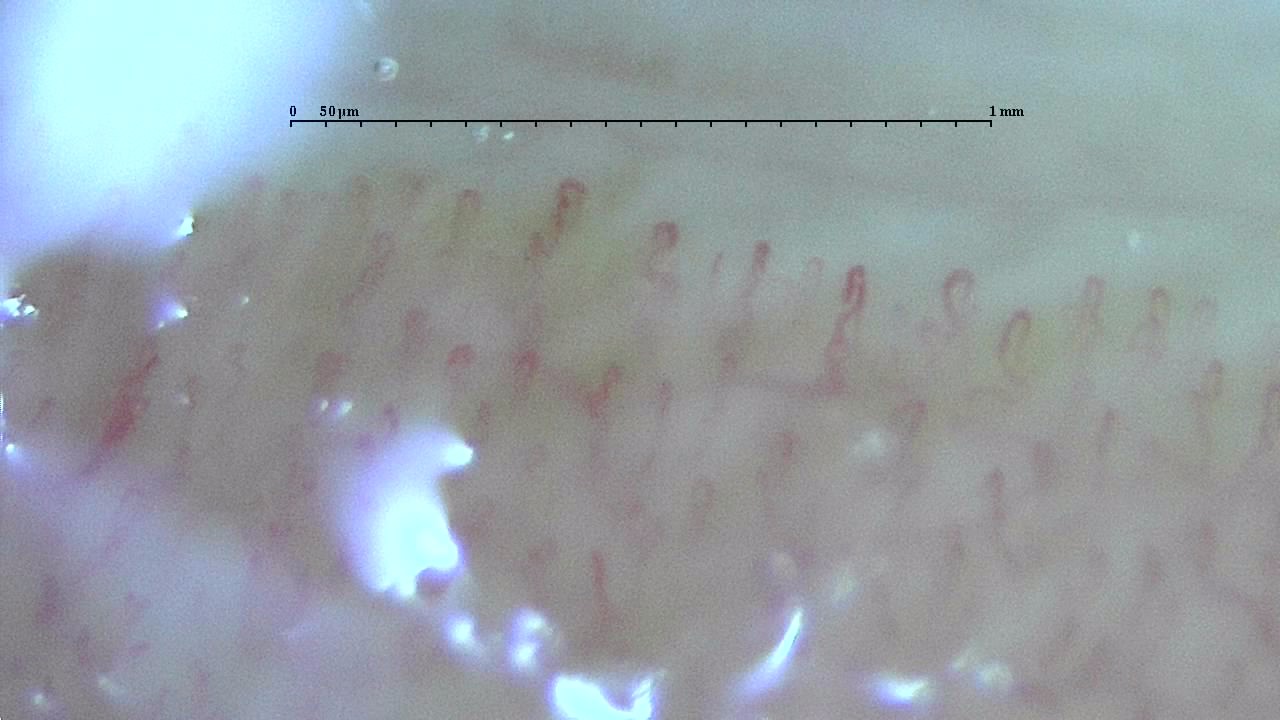

さまざまな毛細血管

さまざまな毛細血管の写真を掲載しました。

いろんな形をしていますね!

上の4枚は、まっすぐ伸びている長さがありキレイな血管といえるでしょう。

スケールは1mmの幅で、1目盛50μmです。

一般的に毛細血管は1mmの中に7から10本程度が正常です。

それを下回る本数であれば、血管が少ないと判断され「冷え性」である可能性が高くなります。

上4枚と下4枚を比較

上の4枚と比較して下の4枚はどうでしょう?

よじれがあったり、本数が少ない長さが足りないなどさまざま。